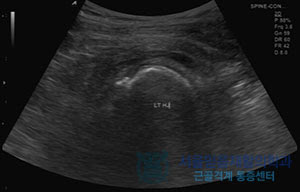

고관절 통증의 원인

고관절의 통증은 매우 다양하고 여러 가지 원인에 의해 발생할 수 있습니다. 이러한 원인을 이해하는 것은 통증을 관리하고 예방하는 데 매우 중요합니다.